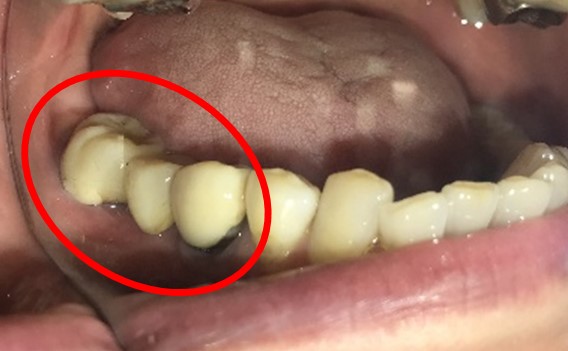

ブリッジの支台になっている奥の歯が、被せ物の中で虫歯になり、支台の役割を果たさず、前方の歯のみで支えられていました。前方の歯をそのままにして、後方の部分を切り離すと、そのまま取れてきました。中は、虫歯で歯根しか残っていない状況でした。この歯は、根管治療後、単独でオールセラミック冠を被せ、歯のないところにインプラントを埋入しました。

冠の中で大きな虫歯になり支台の役割を果たしていませんでした。

冠はブリッジを切断しただけで取れてきました。軟化象牙質を取り除いたところ、歯根しか残っていない状況で保存できるかどうかのぎりぎりのところでした。